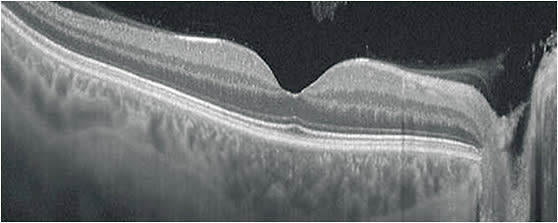

Another very common problem I have witnessed is variable results in optical coherence tomography (OCT) imaging. Since OCT was introduced to ophthalmology, it has become the most widely utilized diagnostic imaging device in ophthalmology. Device manufacturers have streamlined the acquisition process as best they could, but without proper training, a technician may not produce quality images.

For example, in the case of OCT, it is critical to understand that near-infrared light is used to document tissue. The user who understands how OCT produces an image will know that anything affecting light will affect the OCT image. This principle applies to dry eye, cataract, and other factors that influence the media that the light passes through. Recognizing ocular anatomy and understanding how pathology affects a patient’s fixation are basic tools needed to produce quality images.

In addition, note that a clean, crisp image is not necessarily indicative of a quality image. Proper placement and repeatability of a scan is the foundation of a quality image. This applies to retina scans as well as glaucoma scans. OCT devices are incredibly sensitive, and can measure change to a micron, but if the scans are not repeated in an exact, standardized fashion, it doesn’t matter how good the scan looks. The data will be false and could be used by the clinician to stop or initiate a treatment that the clinician otherwise would not do.